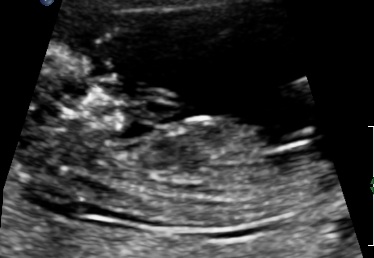

Well went for my scan today, baby was very photogenic! I was exactly 13 weeks.

Not sure what i feel, i am so in love with this baby already. Its funny coz even tho I swayed i am realy not bothered about gender, will not be finding out gender until birth but still would love guesses. Tech gave me her feeling what she thought.

Attachment 3732Attachment 3733Attachment 3734